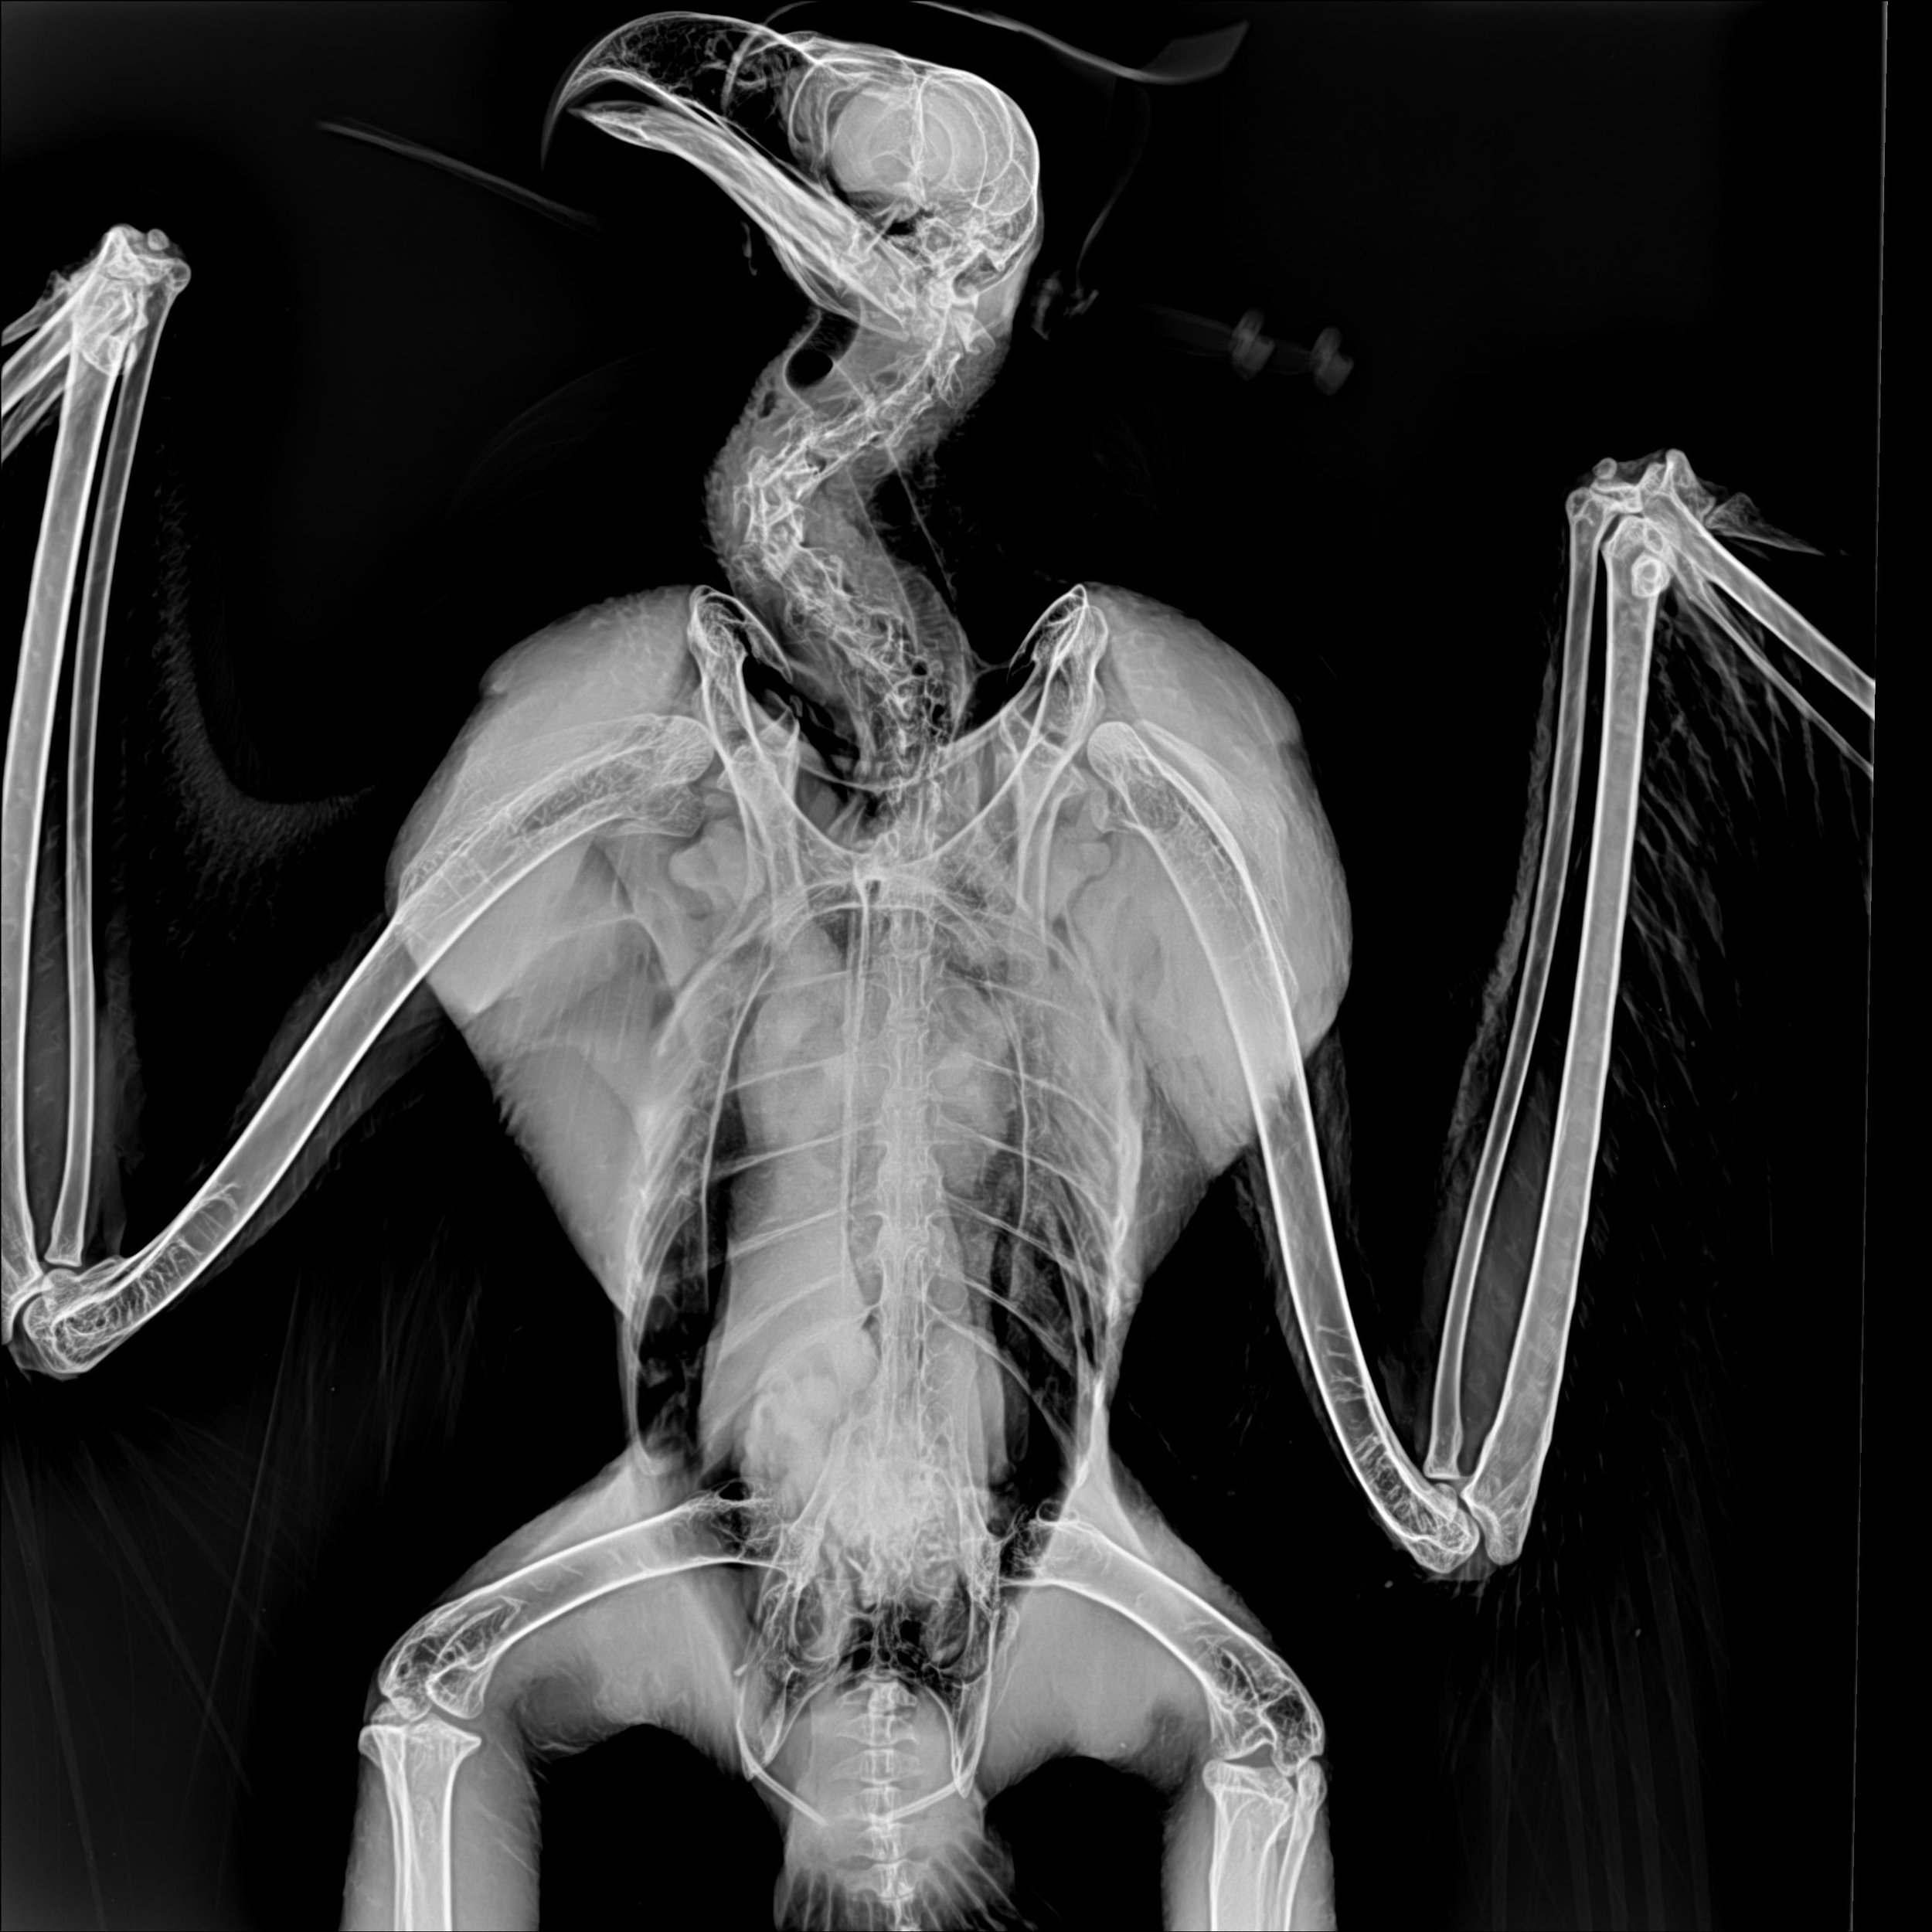

Why was this eagle poisoned? In his X-ray, there were no physical heavy metals noticeable, such as bullet fragments, so we’re not sure how he ended up with lead poisoning. The most common causes are being shot with lead ammunition or consuming lead fishing gear or fish that consumed lead fishing gear.